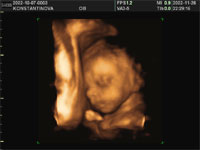

Конечно же, это в первую очередь получило свое применение в акушерской практике. Зарождение человеческой жизни - великое таинство природы. Но, все-таки, гораздо спокойнее, когда знаешь, что происходит внутри тебя. С помощью трехмерного УЗИ будущая мама может увидеть изображение своего ребенка, близкое к фотографии, и получить видеозапись его движений в реальном времени. Данное исследование можно пройти несколько раз в ходе беременности и пронаблюдать основные этапы формирования плода.

К 12-ой неделе можно увидеть уже сформировавшееся тело плода: голову, туловище, руки, ноги, глаза, нос, рот, уши. На экране виден плод целиком, причем рассмотреть его можно со всех сторон. В 20 недель возможно уже различить каждый пальчик. К 5 месяцам плод заметно вырос, он двигается, совершая координированные движения, принимает различные позы, сосет пальчик, закрывает лицо руками. К 28 неделе у плода округляются щечки, лицо становится более сформированным, различимы губы, нос. Он может почесать ухо, сложить кулачки, зевнуть, состроить гримасу, улыбнуться. И это все будущая мама видит на экране в реальном времени.